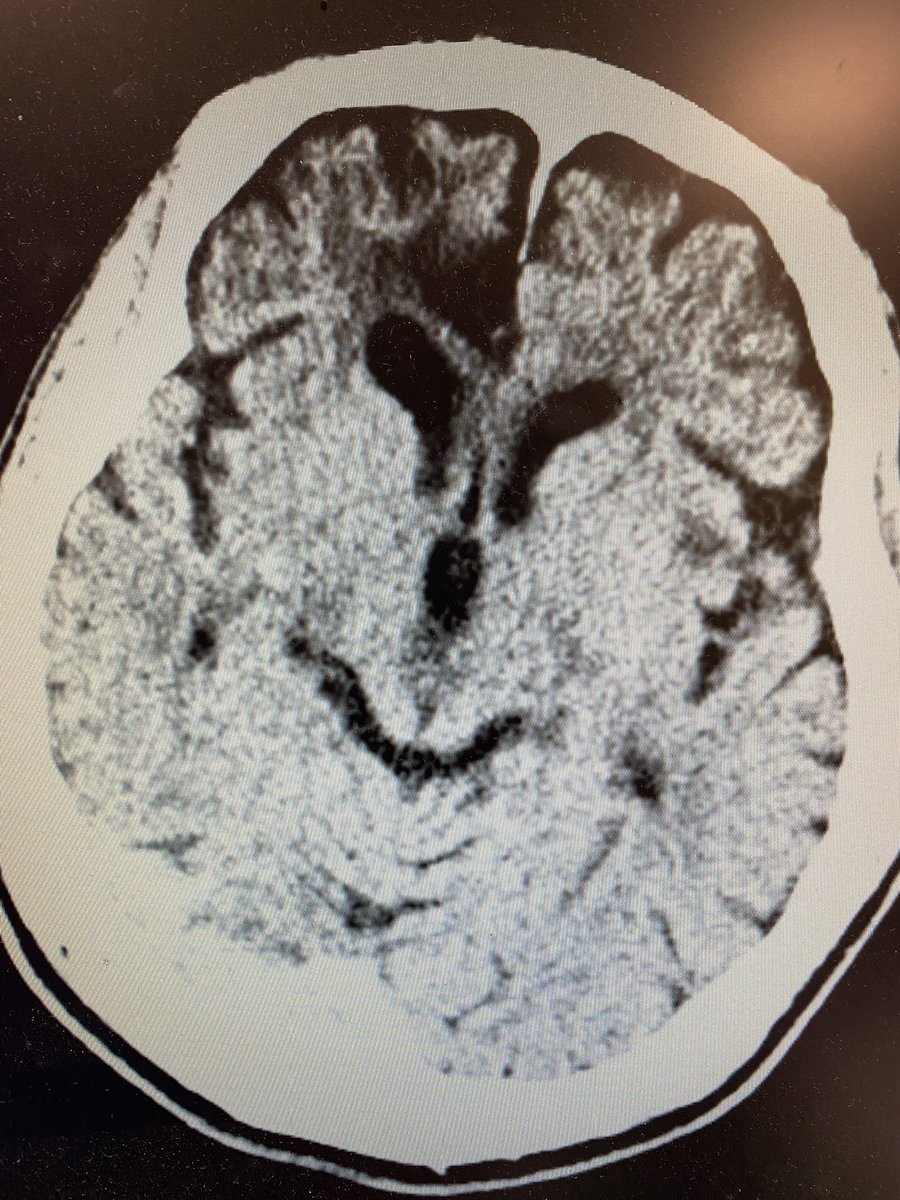

Initial CT head reveals prior right frontal encephalomalacia but no hemorrhage. CTA does not reveal any large vessel occlusion. EEG reveals slowing, generalized, excess beta, no epileptic Discharges or seizures 4/x

What is your diagnosis now? Only one left is serotonin syndrome which would fit except for the right pupil… Repeat ct now makes diagnosis clearer and mri confirms 5/x